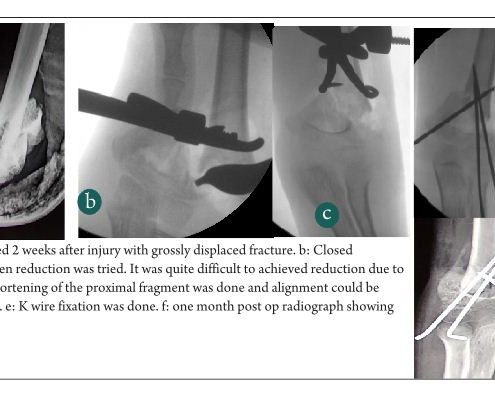

Delayed presentation of SC fractures – Open Reduce now or accept for Future Osteotomy

Vol 1 | Issue 1 | July-Sep 2015 | page:23-25 | Premal Naik,…